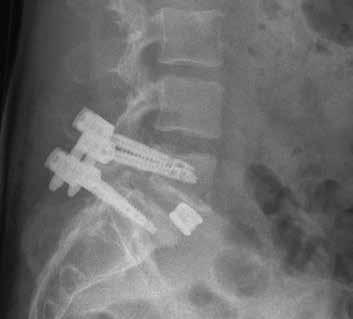

Een spondylodese is een operatie waarbij twee of meerdere wervels worden vastgezet. Zo’n fusie is een bewezen effectieve methode voor het verminderen van pijnklachten en het verbeteren van het functioneren bij een lumbale spondylolisthesis. Met behulp van observationeel onderzoek wordt in Nij Smellinghe sinds 2021 geprobeerd de patiëntreis rondom deze ingreep te verbeteren. Deze casus beschrijft het traject rondom de ingreep van een patiënt die een fusie kreeg op niveau L5-S1.

Wanneer een te grote beweeglijkheid van de wervels ontstaat, kan dit leiden tot instabiliteit van de wervelkolom. Deze instabiliteit kan veroorzaakt worden door een spondylolyse of een spondylolisthesis. Hierdoor raken zenuwen bekneld, wat kan leiden tot pijnklachten in de lage rug en sensorische en motorische stoornissen in één of beide benen. Door de betrok-

ken wervels te fixeren met behulp van osteosynthesemateriaal is de instabiliteit te verhelpen. Daarmee verbetert het lichamelijk functioneren en verminderen de pijnklachten.1 Deze ingreep wordt al vele jaren gedaan, maar wint de laatste tijd sterk aan populariteit. Er komen namelijk steeds meer moderne materialen beschikbaar die de ingreep veiliger en effectiever maken.2 In de Verenigde Staten is het aantal lumbale spondylodeses gestegen van 122.679 in 2004

naar 199.140 in 2015.3 Het is niet bekend hoeveel van deze ingrepen jaarlijks in Nederland worden uitgevoerd.

Voorlichting en behandeldoelen De neurochirurg heeft Teun na het klinisch onderzoek en beeldvorming gediagnosticeerd met een anterieure afschuiving van L5 ten opzichte van S1 met indicatie voor een minimaal invasieve Transforaminal Lumbar Interbody Fusion (TLIF)-spondylodese ter hoogte van L5-S1. Als aanvulling wordt Teun verwezen naar de fysiotherapeut voor een preoperatieve screening. Bij de fysiotherapeut krijgt Teun uitleg over de gehele patiëntreis en hoe hij zelfregie kan nemen in het traject voor, tijdens en na de operatie. Veel aandacht gaat uit naar pijneducatie en grenshantering. Daarnaast krijgt Teun aan de hand van een patiëntfolder uitgebreide voorlichting over de opnameperiode. De hierin beschreven oefeningen voor na de operatie worden ook doorgenomen. Bovendien komen de leefregels voor na de operatie aan bod. De eerste zes weken mag Teun niet langer dan twintig minuten achter elkaar zitten. Ook mag hij niet fietsen, zwemmen, autorijden en werkzaamheden verrichten die de rug belasten, zoals

In september 2021 wordt Teun opgenomen voor de operatie. Hij meldt zich in de vroege ochtend op de verpleegafdeling van Neurologie. De operatie vindt in de ochtend plaats en duurt ongeveer vier uur. De operatie verloopt zonder complicaties. Voordat de incisies worden gesloten laat de neurochirurg pijnmedicatie achter in het operatiegebied. Hierdoor heeft de patiënt postoperatief minder pijnklachten en is hij sneller in staat om te starten met mobiliseren. Gedurende de opname krijgt Teun pijnmedicatie op basis van zijn pijnervaring.